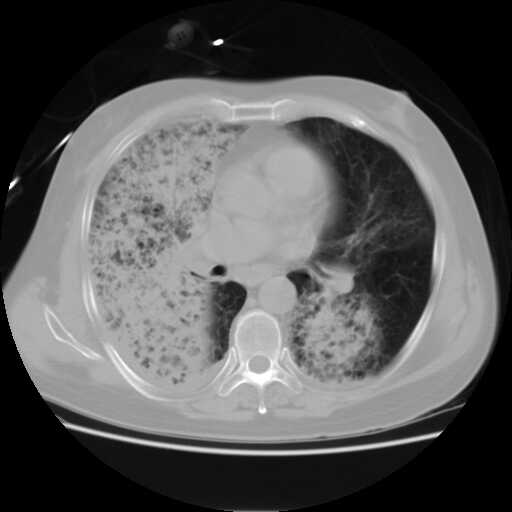

2008.8.17ct定位片

2008.8.17ct

病变从8.11-8.17明显改变,增多,以蜂窝状改变为主,类蜂窝肺,似弥漫性肺泡癌,但是病变进展太快,不符合弥漫性细支气管肺泡癌。因此考虑为特殊微生物感染,多以霉菌类常见,建议细菌微生物学检查。

追踪结果,该病人已于2008.8.18日经抢救无效死亡.死于呼吸衰竭.具体病因不明,未作死体解剖.

疑点二:影象表现怪异,大片阴影内见多发筛孔征,如何解释.